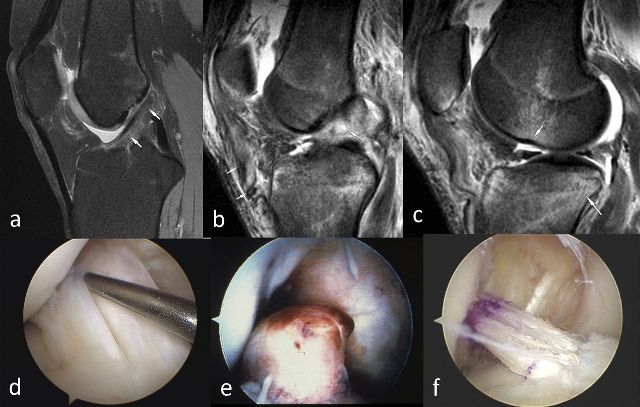

Диагноз выставляется на основании результатов инструментальных исследований. Внешний осмотр, функциональные тесты малоинформативны, так как под клинические проявления болезни Гоффа могут маскироваться бурситы, синовиты, гонартроз, ревматоидный, реактивный или инфекционный артрит. Назначается проведение МРТ или КТ. Исследования позволяют оценить состояние жировой клетчатки, установить стадию воспалительного процесса и степень поражения тканей.

При необходимости назначается артроскопия — минимально инвазивная хирургическая манипуляция, которая проводится для обследования внутренних поверхностей сустава. Рентгенография показана для дифференциации болезни Гоффа от патологий, поражающих костные и хрящевые ткани.

При неэффективности консервативной терапии, быстром прогрессировании болезни Гоффа, развившихся осложнениях пациенту показано хирургическое вмешательство. В большинстве случаев проводится артроскопическая операция. На коже над коленом хирург делает несколько проколов под общей анестезией. Через них вводятся артроскопические инструменты, с помощью которых он совершает манипуляции. За ходом операции хирург следит по монитору. Изображение на него передается с миниатюрной видеокамеры, перемещающейся внутри сустава.

Хирург иссекает ткани, подвергшиеся перерождению или зажатые между костными поверхностями. Проведение операции малоинвазивным способом позволяет избежать отделения большого количества крови и сильного повреждения мягких тканей.

- МРТ — определяется патологическая динамика в суставных тканях, в том числе объем разрастания жировых тел.

Наиболее эффективным методом оперативного вмешательства считается артороскопия. В колене делаются небольшие проколы, через которые в сустав вводят инструменты и миниатюрную видеокамеру, при помощи которой все манипуляции хирурга отображаются на мониторе. Врач удаляет фиброзные разрастания и излишнюю жировую клетчатку. Некоторую ее часть оставляют, чтобы она могла разрастись в дальнейшем в полноценные тела Гоффа.

- Магнитно-резонансная томография – наиболее точный вид исследований, который определяет состояние сустава, степень вовлеченности жировых тел Гоффа в воспалительный процесс и его обширность;

- Артроскопия – вскрытие пораженного сустава и его осмотр;

Если ни один из неинвазивных диагностических методов не дал возможности точно поставить диагноз, требуется артроскопия. Операцию проводят под общим наркозом и зачастую сразу совмещают с лечебными процедурами.

Артроскопию коленного сустава при болезни Гоффа (операцию эктомии жирового тела) делают тогда, когда консервативное прохождение реабилитации не дало положительного эффекта. Применяется эндоскопический способ проведения операции — артроскопия. Пациентами неплохо переносится лечение. Этот прием используют и для диагностик, и для проведения операции.

- С целью диагностики совершают 2 прокола по 5 миллиметров, вводят в них миниатюрные камеры и выводят внутреннее изображение коленного сустава на дисплей.